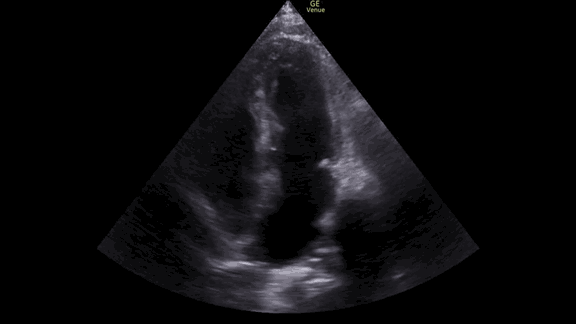

Although he did not have beautiful ultrasound windows, we were able to see enough to make some decisions.

The apical 4 chamber view of the heart showed, as expected, a hyper-dynamic heart with a grossly normal ejection fraction.